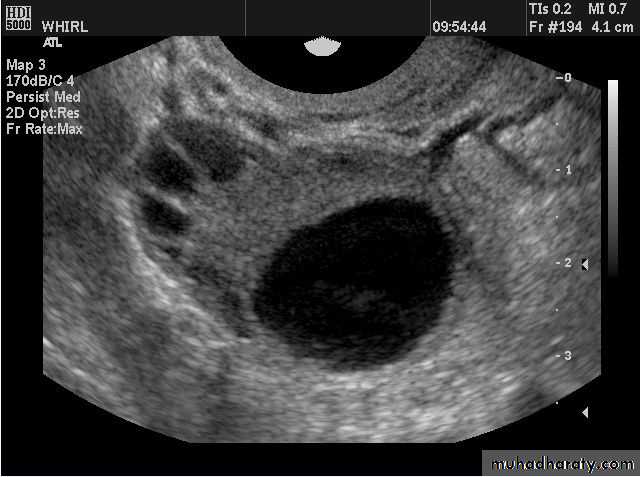

Functional cysts of the ovary - Follicular cysts:

This young female patient underwent sonography for non-specific pain in the lower abdomen. Ultrasound images of the pelvis show bilateral ovarian cysts which show absence of internal nodules, septae or debris. These findings are typical of follicular cysts of the ovaries. Follicular cysts are functional cysts and are enlarged ovarian follicles that have not ruptured (ovulated). They are usually unilateral.